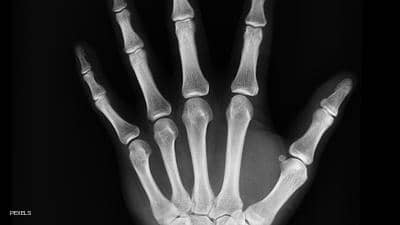

فحص الكثافة

يمكن للأطباء الحصول على صورة أشعة سريعة للتأكد من أن كثافة العظام سليمة. ويساعد هذا الفحص في تحديد مخاطر الإصابة بمرض هشاشة العظام والكسور.